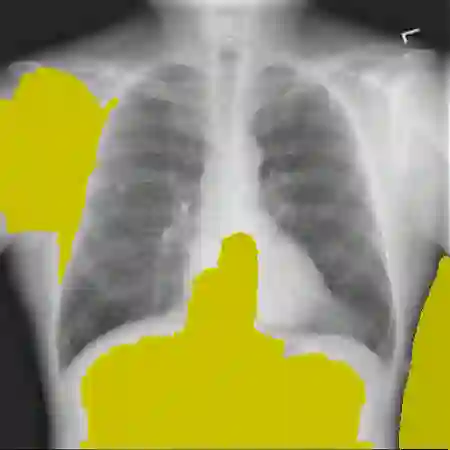

The remarkable success of deep learning has prompted interest in its application to medical imaging diagnosis. Even though state-of-the-art deep learning models have achieved human-level accuracy on the classification of different types of medical data, these models are hardly adopted in clinical workflows, mainly due to their lack of interpretability. The black-box-ness of deep learning models has raised the need for devising strategies to explain the decision process of these models, leading to the creation of the topic of eXplainable Artificial Intelligence (XAI). In this context, we provide a thorough survey of XAI applied to medical imaging diagnosis, including visual, textual, example-based and concept-based explanation methods. Moreover, this work reviews the existing medical imaging datasets and the existing metrics for evaluating the quality of the explanations. In addition, we include a performance comparison among a set of report generation-based methods. Finally, the major challenges in applying XAI to medical imaging and the future research directions on the topic are also discussed.